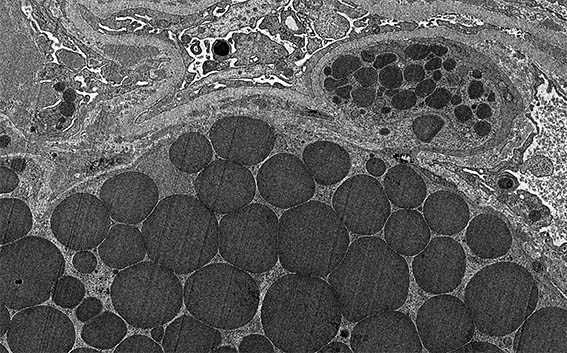

Figura 11. Microscopía electrónica, aumento original, X1.500.

Figura 12. Microscopía electrónica, aumento original, X2.100.

Figura 13. Microscopía electrónica, aumento original, X1.500.

Figura 14. Microscopía electrónica, aumento original, X4.000. Los gránulos o cristales están en el citoplasma de células intracapilares.